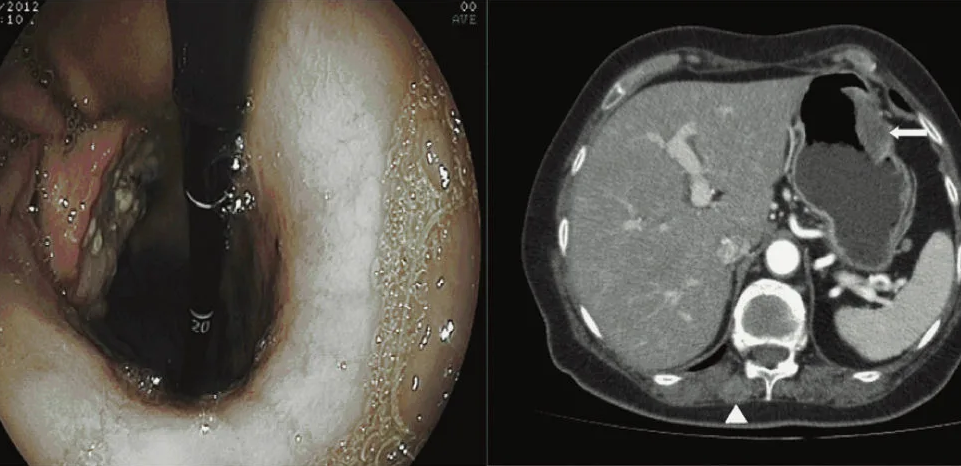

Магнитно-резонансная томография (МРТ):один из самых эффективных методов диагностики заболеваний